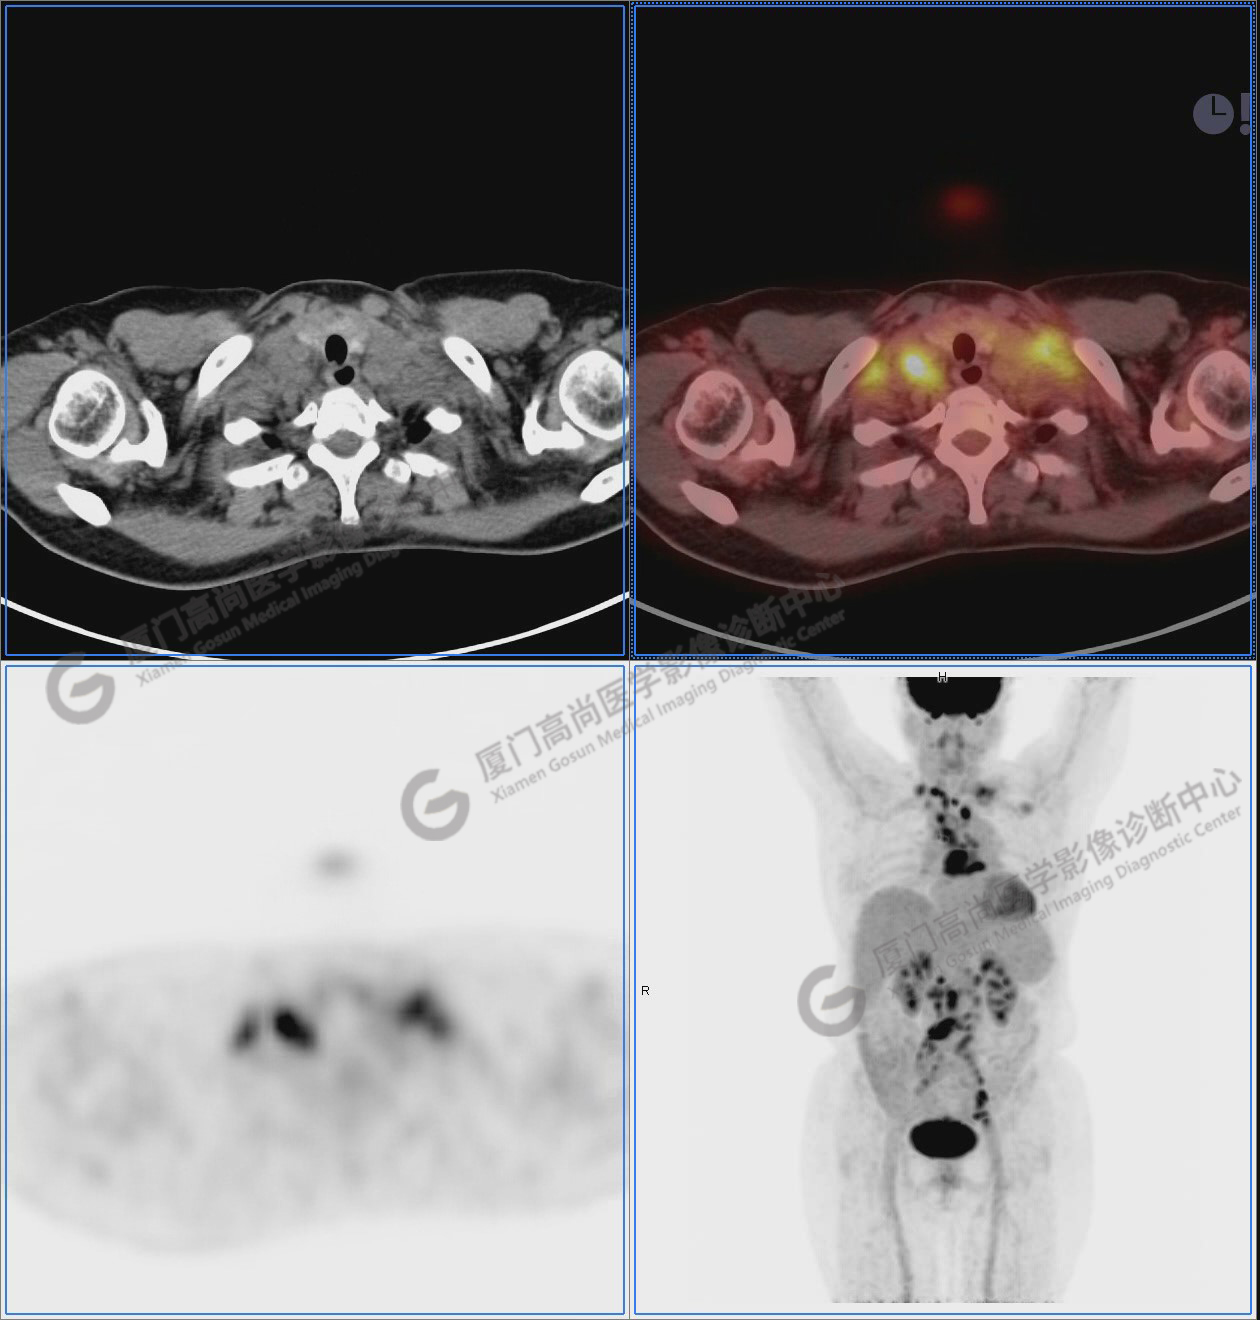

圖1:PET/CT全身圖像

圖2-9:雙側(cè)鎖骨區(qū)、縱隔、右側(cè)內(nèi)乳區(qū)、腸系膜緣、腹膜后、雙側(cè)髂血管旁及盆腔多發(fā)腫大淋巴結(jié)影,代謝不同程度增高,考慮為轉(zhuǎn)移。